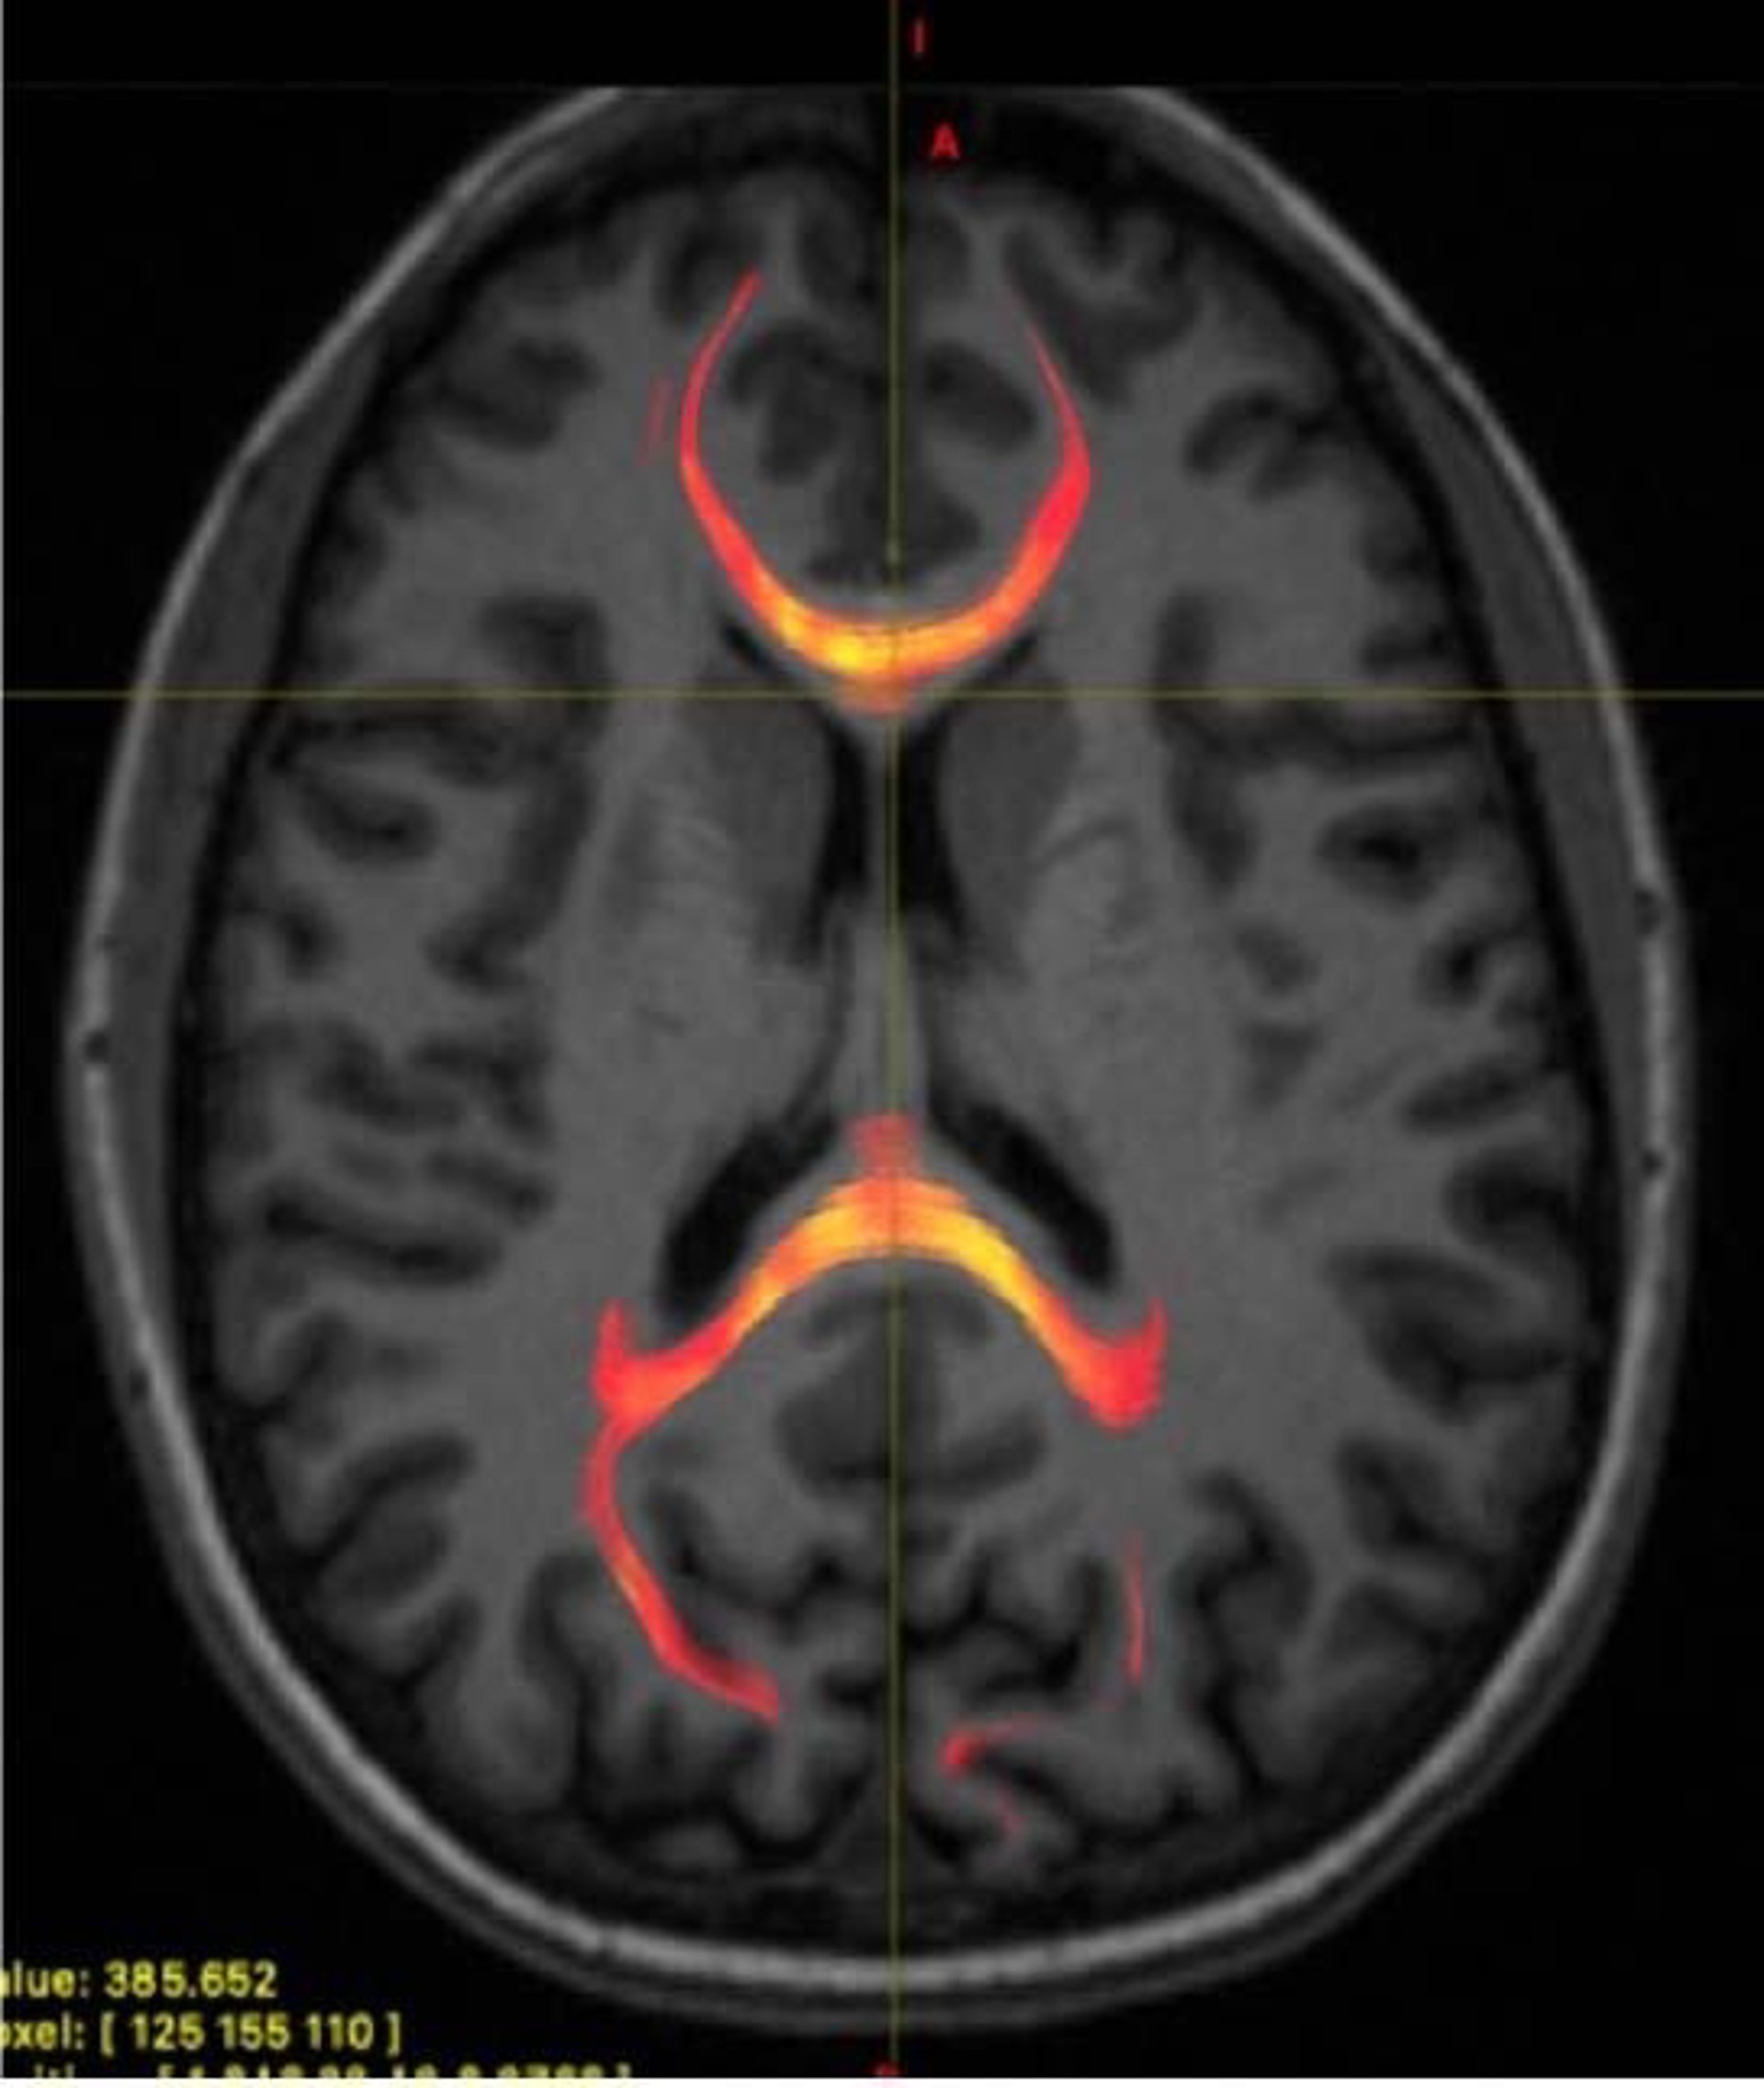

La lesión cerebral traumática leve es difícil de detectar con los métodos de imagen convencionales actuales. De hecho, la mayoría de los pacientes no presentan daño estructural visible en el cerebro, el cual podría detectarse mediante tomografía computarizada.